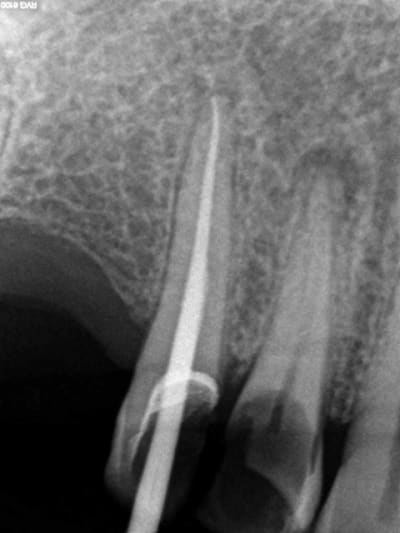

Aujourd'hui patient en urgence ca tombe bien pour une fois synchro avec un lapin.

45 mn de turbinage intensif 2 endos + 2 SC 33; On cote comment les radios ?

Z6, SC 20, Z3,Z3, SC20, Z3, Z3, SC 33, Z3, SC 33, Z3 ?

Tssss, Z6 radio de diagnostic, endo Z3 + Z3 par endo, SC33 radios de controle Z3, 1 par acte.

Avant c'était Z6 par séance quel que soit le nombre de clichés. Je n'ai pas fait les 2 endos en meme temps simplement la première à été faite en mode turbo, j'avais donc du temps en rab et j'ai fait la seconde après. A la limite un Z 3 de trop sur les SC 33.